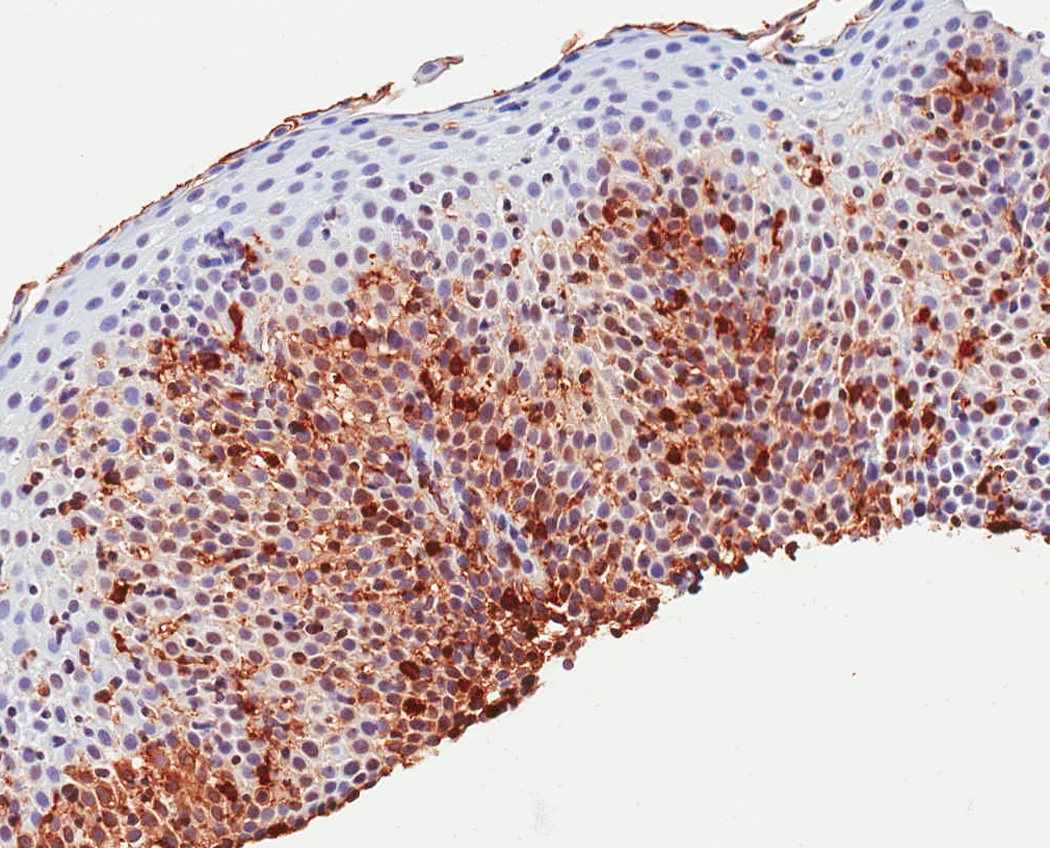

In a protocol identical to that for eosinophil counts, the IHC glass slides were scanned and converted to digital slides, and viewed with Aperio ImageScope (Aperio Technologies, Vista, CA) (24). The maximum density of tryptase-positive cells in the esophageal epithelial layer, measured in mast cells/mm2, was then determined after examination of five microscopy fields. This quantitative measure of tryptase-positive mast cell density was the primary predictor variable for the study. In addition, we assessed the mucosal and biopsy distribution of mast cells, and made an assessment of staining intensity, which ranged from grade 0, or no staining, to grade 4, or diffuse staining (Figure 1). These are presented to provide examples of the overall range of possible staining results.

Figure 1.

Observed range of staining of tryptase-positive mast cells in the esophageal epithelium. (A) Grade 0 – no staining. (B) Grade 1 – minimal staining in the basal zone. (C) Grade 2 – moderate staining, but still patchy. (D) Grade 3 – more prominent staining spread throughout the epithelium. (E) Grade 4 – marked and diffuse staining.